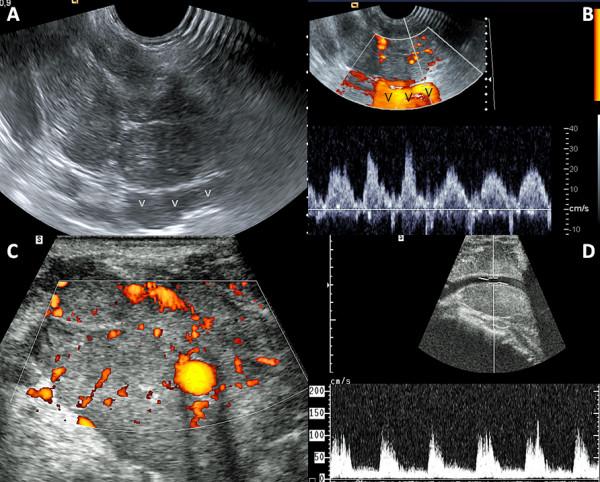

Of 1171 patients with thyroid cancer treated at our institution over the last 18 years, we retrospectively identified nine patients (0.8%), three women and six men, aged 34-81 years (median age: 70 years) presenting with malignant thyroid tumor of median diameter 45 mm (range: 23-87) having venous obstruction of thyroid malignancy origin. Two patients underwent multimodal therapy. All other patients underwent external beam radiation therapy alone +/- chemotherapy or palliative care. Ultrasound (US) provided particularly useful information on venous involvement characteristics. Median survival was 7 months and median progression-free survival was 6 months. Survival in our series was worse than that of previously reported series despite diagnosis of vein involvement at an early stage in 2/3 cases using US.

Despite small numbers of patients, it seems that aggressive treatment modalities including surgery are required to improve survival. In our experience, US was a useful non-invasive method to describe tumor extensions to great veins of the neck (invasion versus compression, tumor thrombus versus blood clot) and should be recommended to depict early venous invasion in cases of suspected thyroid malignancy.